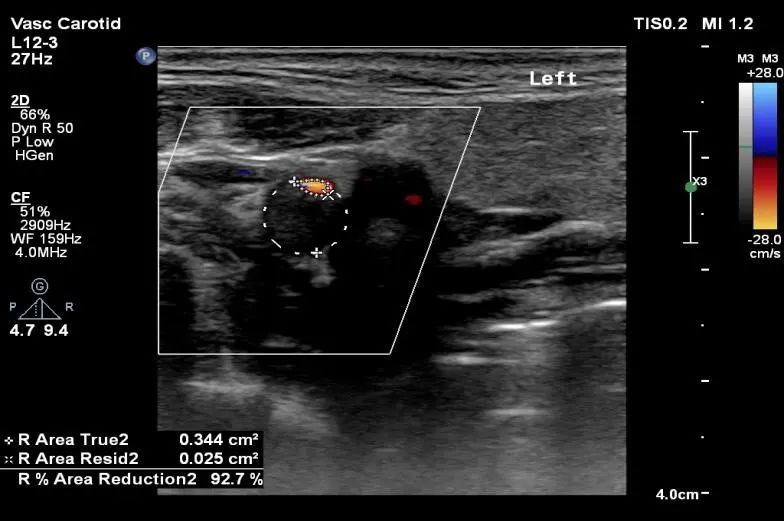

患者,男,52岁,发作性左侧肢体活动不灵就诊。头MRI提示未见异常病灶。TCD提示右侧大脑中动脉重度狭窄。通过血管超声的筛查,找到了临床事件的“始作俑者”-责任血管。

“健康”体检者。颈动脉超声提示颈动脉重度狭窄。TCD提示颅内侧支循环代偿充分。无创的头颈血管超声的一体化评估是筛查脑血管病高危人群的首选,是“前哨兵”。